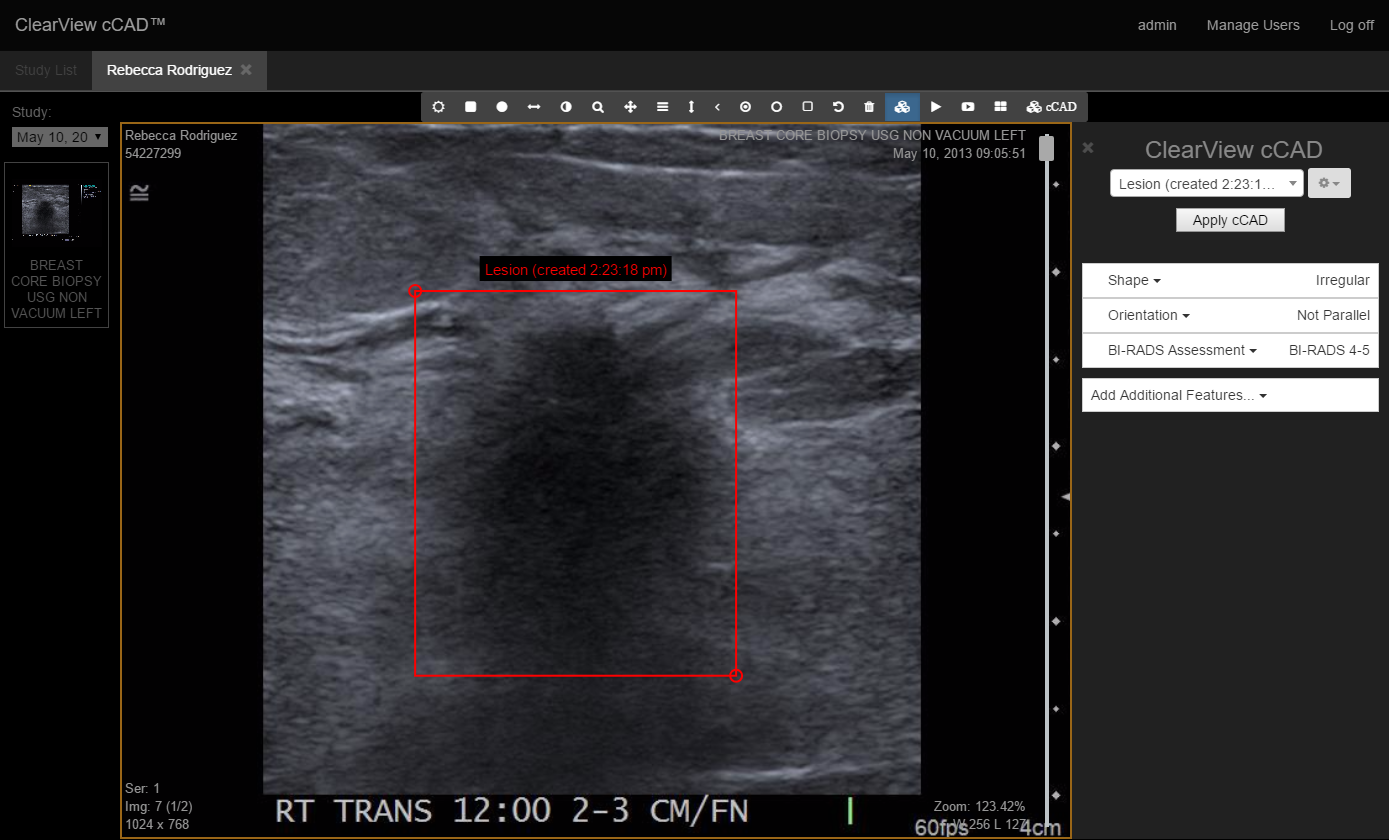

Clearview Diagnostics Inc http://www.clearviewdiagnosticsinc.com/ was formed in 2012 to create clinical decision support systems that help reduce the inter-observer variability of medical imaging diagnosis while improving detection rate and turn around time.

Published studies show the advantages of using cCAD,issued method patent for training machine learning system to compensate for cognitive bias in decision making for the general population , a specific group or an individual diagnostician